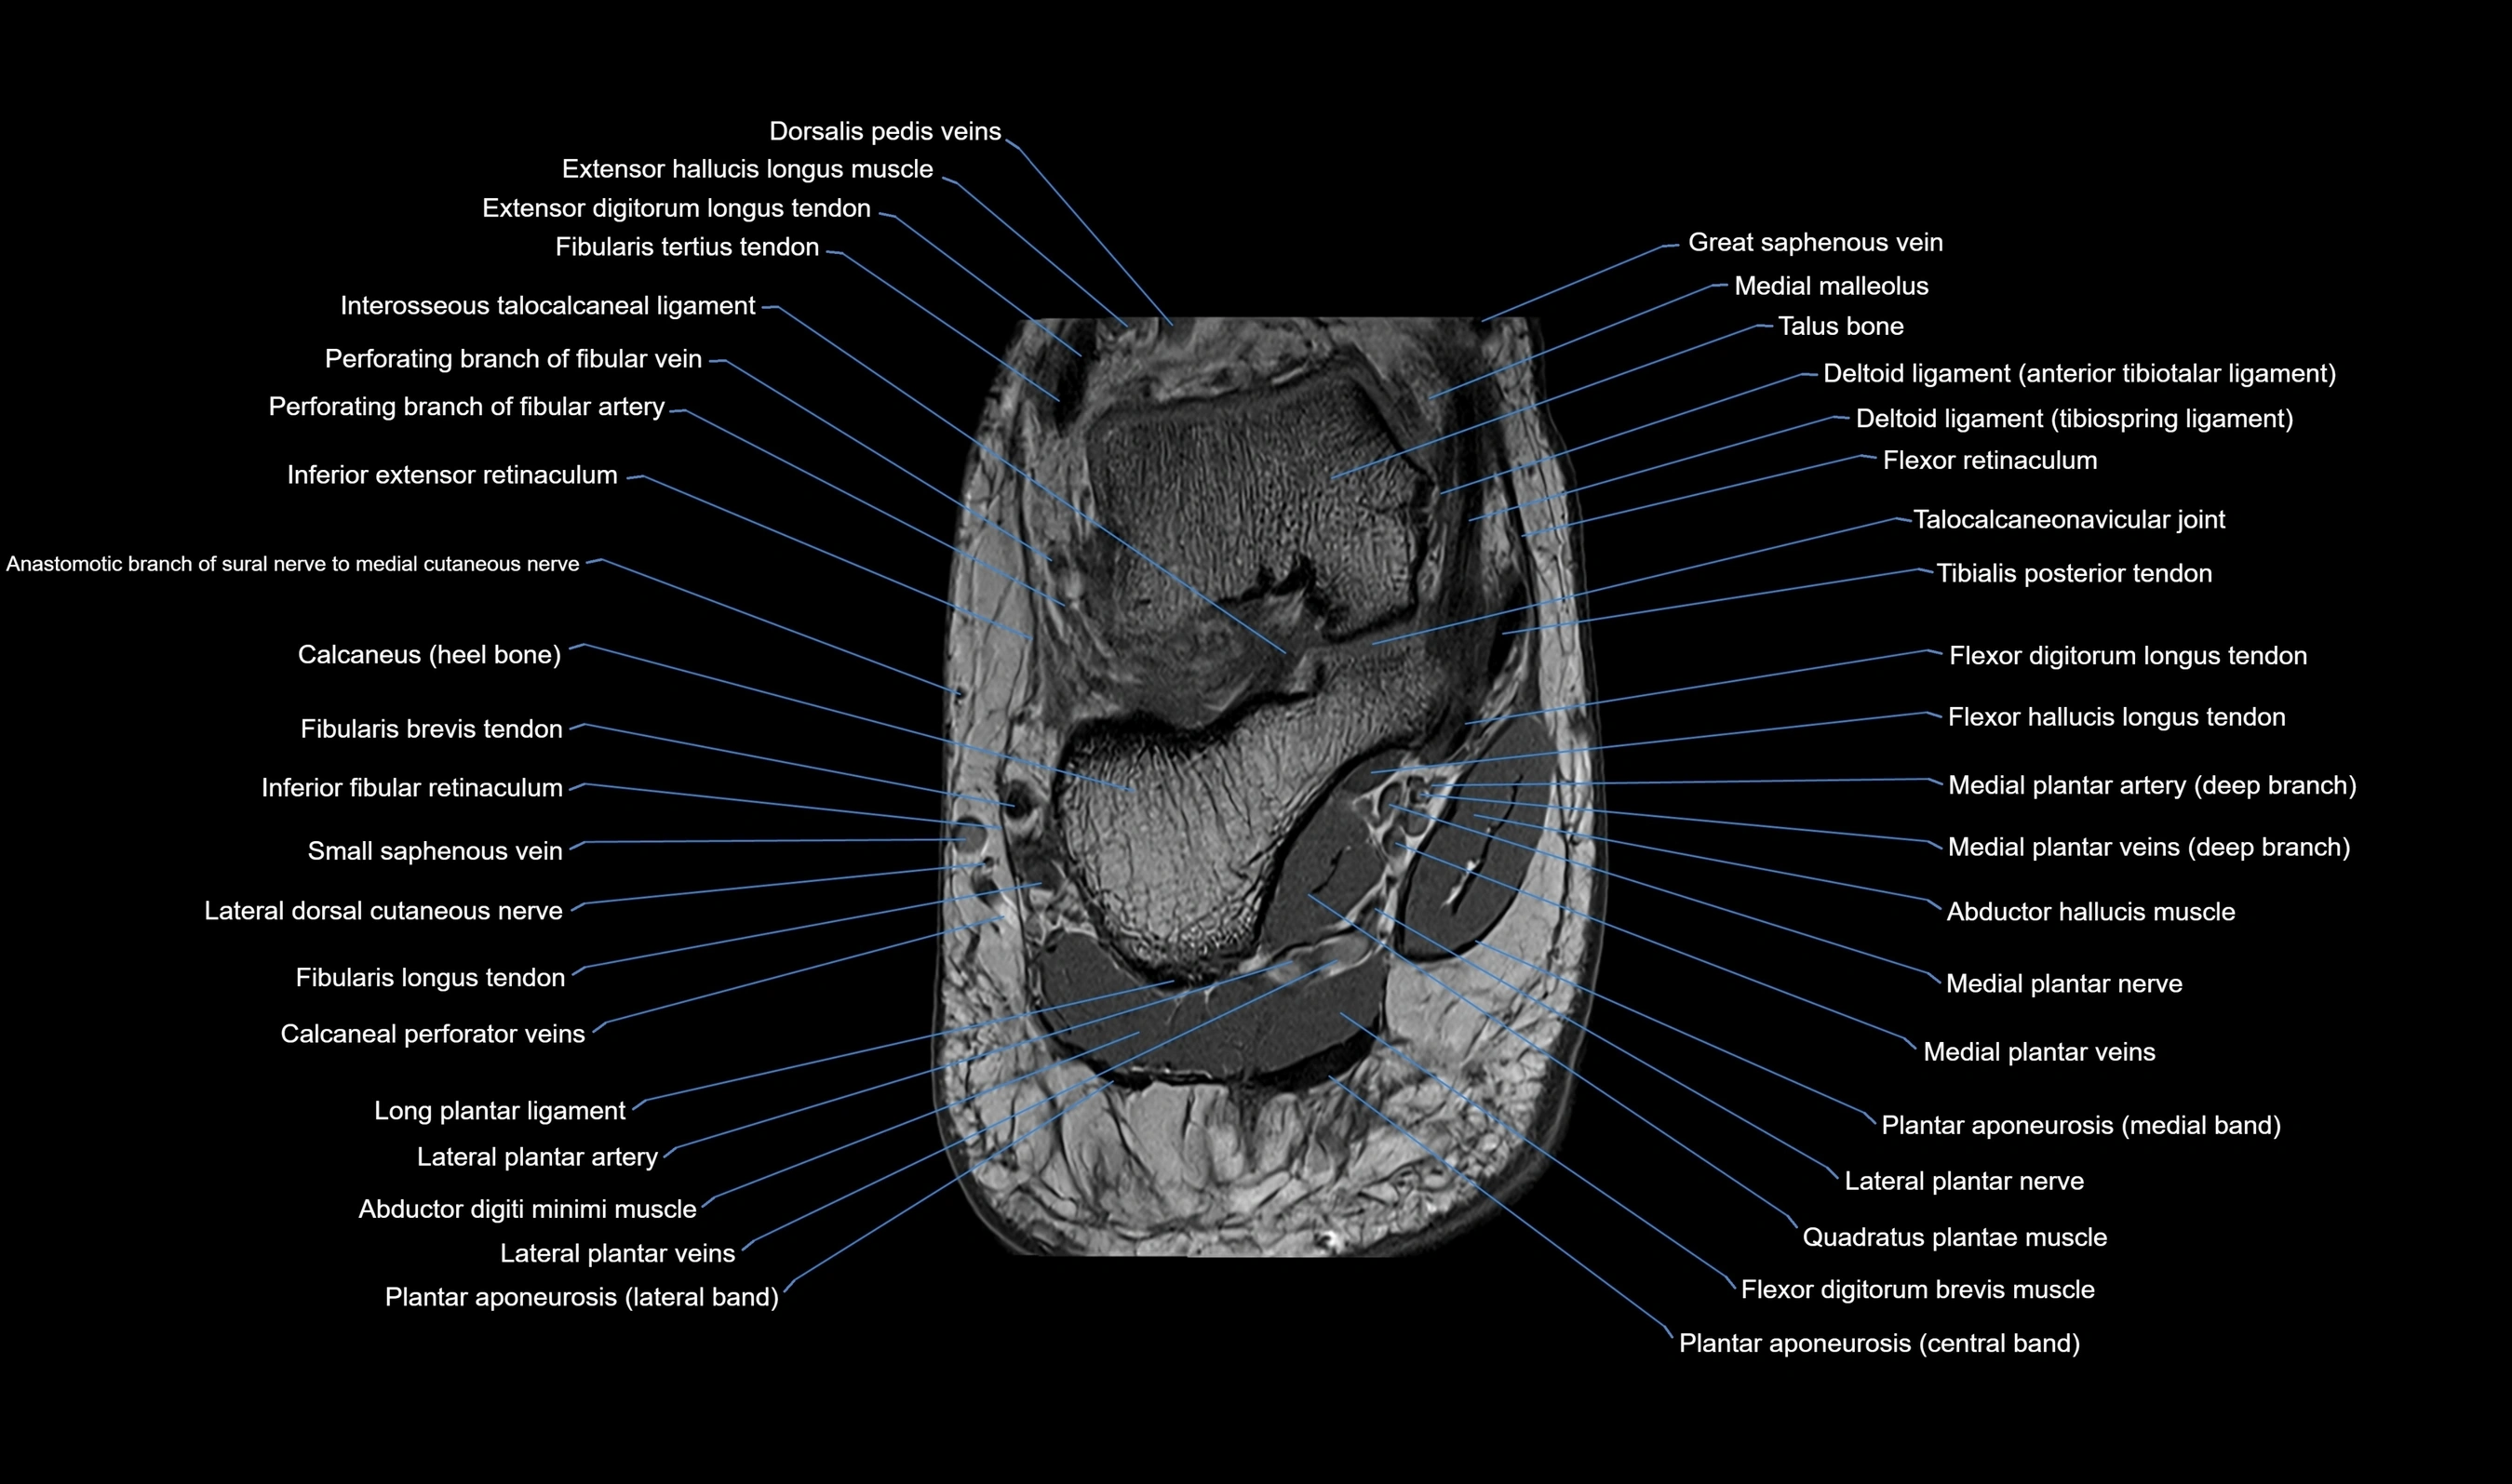

MRI image